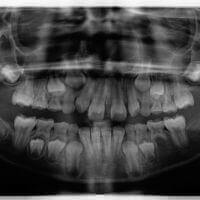

1. Digital X-rays.

Three things that I love about digital x-rays: 1) There is no lag time to develop them — they can be viewed immediately. 2) Patients can see them on a screen (we use I-pads for this purpose). 3) The radiation needed to expose them is about 20% that of traditional film.

Digital Bitewing Xray for seeing in between the teeth.

Adult pano xray for seeing all the teeth at the same time.